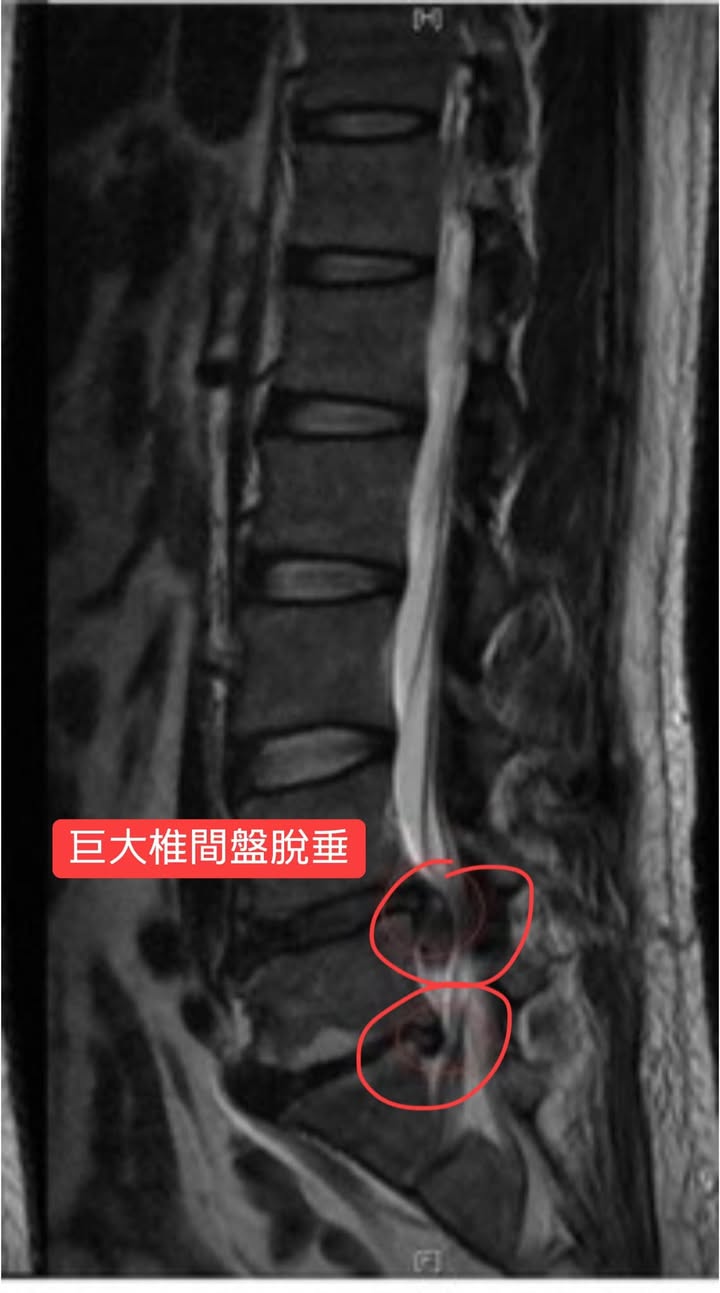

#腰椎間盤巨大突出脫垂

❗️艱難任務巨大椎間盤突出

🔘評估:還沒有馬尾神經症候群

🔜約定治療三週,除非沒有任何改善才考慮神外動刀